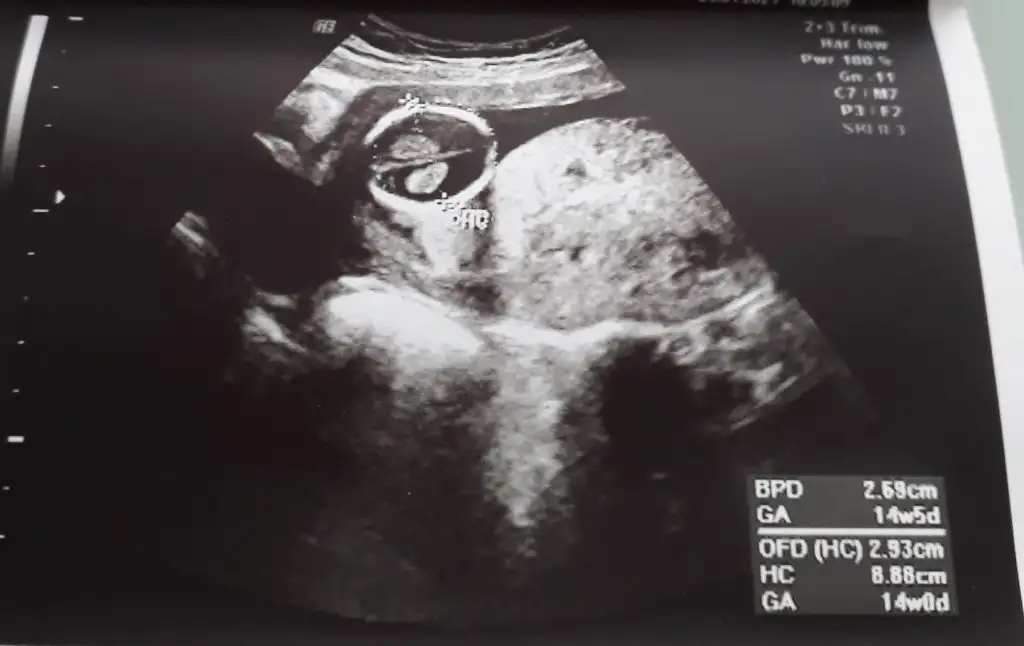

Rabbim sağ salim kucağına almayı nasip etsinValla canım geçen hafta kız dedi bu hafta erkek dedi benim kafa bi milyon şimdi ne diyim bilmedim

Kuzum ben hic anlamam ki usg den, insallah kiz bebektir